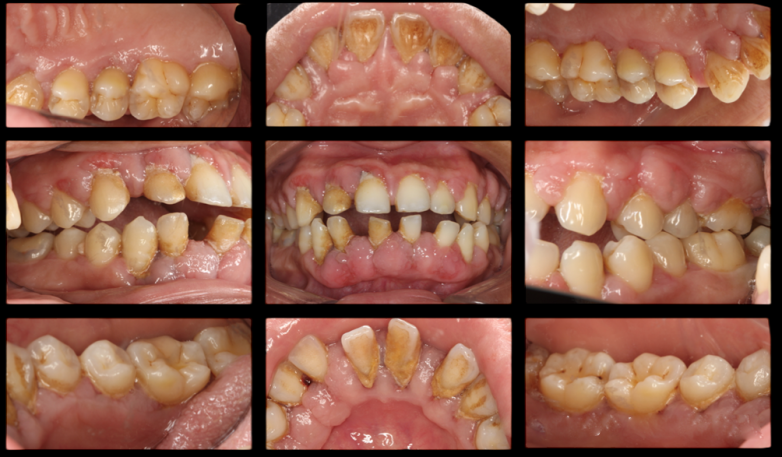

十年前的一个下午,对于34岁的患者(化名:A先生)而言,走进友睦口腔吕达博士的诊室,需要比常人有更多的勇气。此时,他已在肾疾病的阴影下生活多年——肾炎、肾衰竭、高血压,每周需要定期血液透析。更让他困扰的是,治疗高血压的药物带来了新的困扰——伴随三年的药物性牙龈增生。加之未受控制的慢性牙周炎,他的牙龈严重肿大、出血,牙齿也开始移位。

口腔检查结果令人担忧:牙周袋深度5-10+毫米,牙龈球形水肿增生,探诊出血面积达100%,前牙出现明显松动。